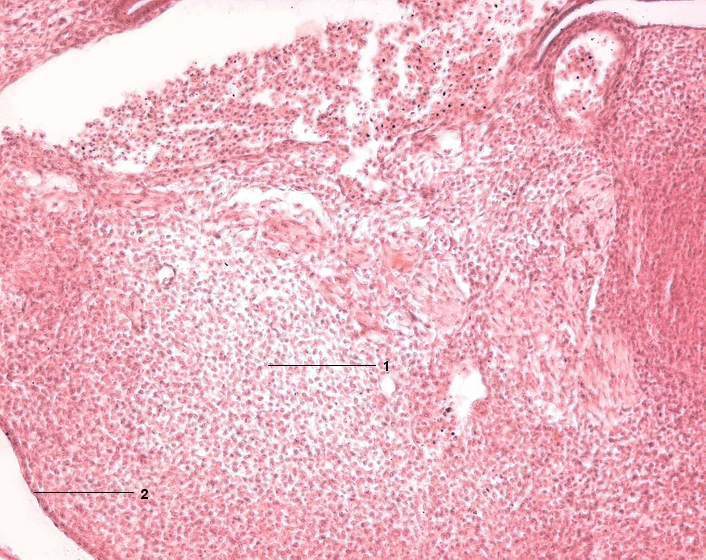

1 Mesenchymales Bindegewebe (Mesenchym)

2 Oberflächenektoderm